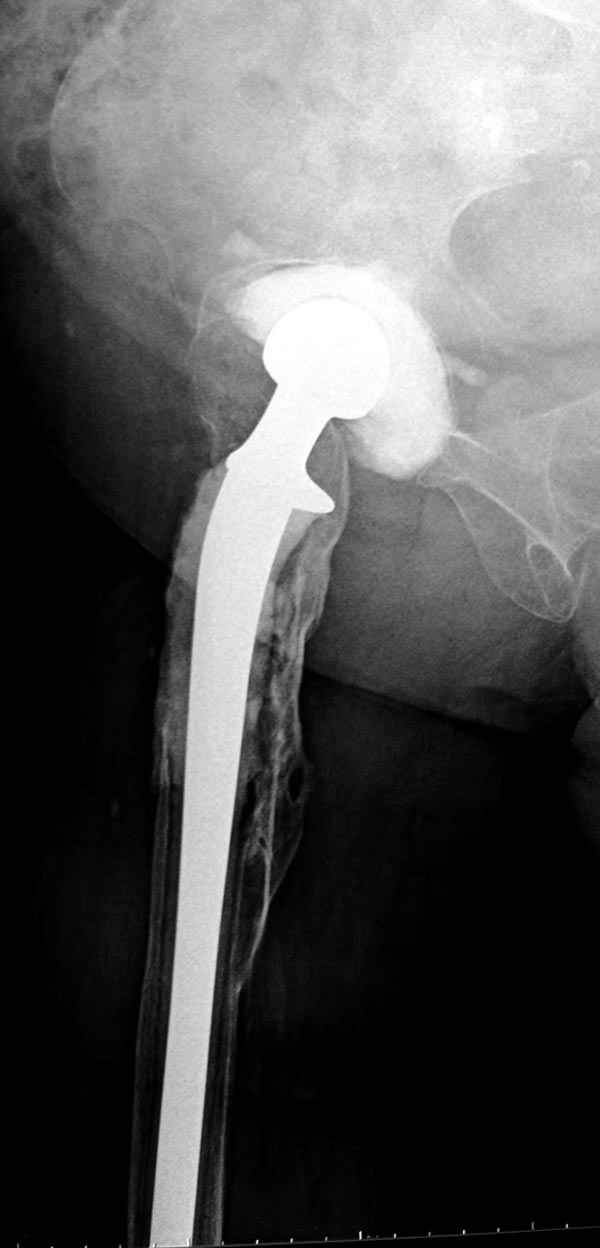

Недавно на сайте выставлял случай восьмилетнего наблюдения после инфицированного эндопротезирования, кроме ножки из цемента с антибиотиком также был сооружен и ацетабулярный компонент.